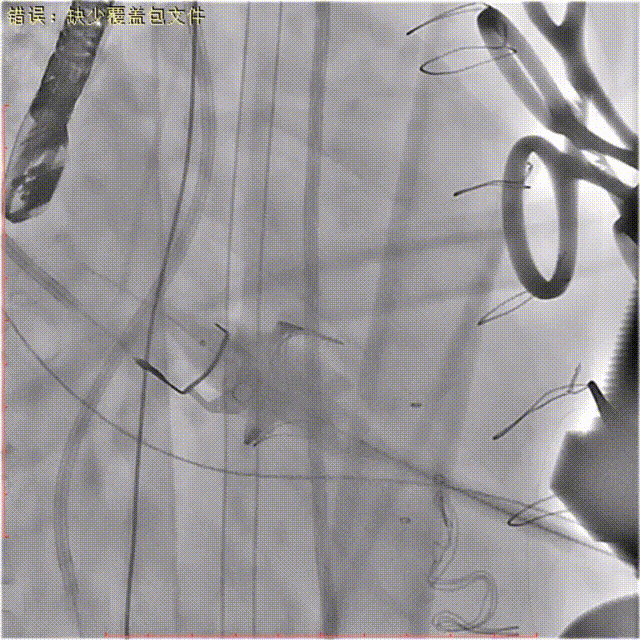

心尖穿刺后置入导丝通过二尖瓣至左房。

球囊预扩

结合术前CT和心超测量的瓣环直径大小,装配好27mm瓣膜,沿加硬导丝送入装备瓣膜的导管输送系统至二尖瓣位置。

送入输送器

释放定位件,确保定位件位于生物瓣瓣窦内,推送植入瓣膜至瓣环平面,打开瓣膜支架,支架释放后退出导管输送系统。

瓣膜定位